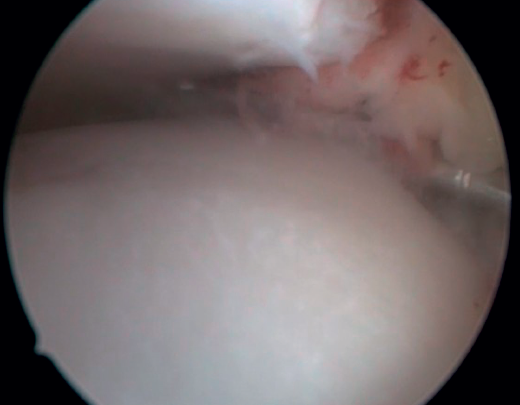

The confirmation of AAI is made by direct vision during arthroscopic examination (Figure 4). This technique allows us to visualise the entire joint, assess the state of the articular cartilage and ligaments, detect the presence of capsular adhesions, synovitis, synovial thickening, loose bodies, etc. It also allows us to carry out functional tests to reveal possible associated instabilities or to assess how the soft tissues causing pain suffer impingement. In our experience, the presence of ATFL lesions is very frequent.

Figure 4. Soft tissue anterolateral impingement in a patient with concomitant anterior talofibular ligament injury who underwent arthroscopic repair associated with resection of the impingement.